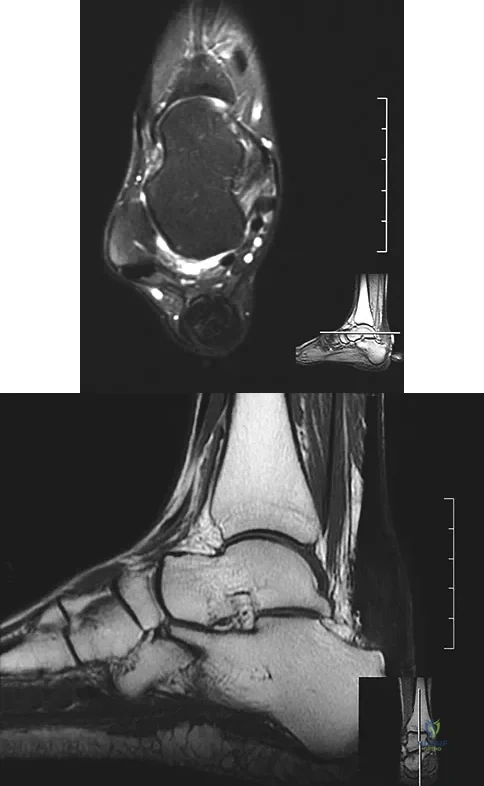

A 22-year-old professional ballet dancer reports a 3-month history of posterior ankle pain that occurs when she changes from a flat foot to pointe (hyperplantar flexed position). Examination does not elicit the pain with forced passive plantar flexion. A radiograph is shown in Figure 8. What is the most likely cause of the pain?

Options:

- Mild subtalar arthritis

- Posterior tibialis tendinitis

- Os trigonum entrapment syndrome

- Flexor hallucis longus tenosynovitis

- Retrocalcaneal bursitis

Correct Answer: Flexor hallucis longus tenosynovitis

Explanation:

The most common causes of posterior ankle pain in ballet dancers are flexor hallucis longus tenosynovitis and os trigonum syndrome. Flexor hallucis longus tenosynovitis differs from a symptomatic os trigonum by the absence of pain with forced plantar flexion and the presence of pain with resisted plantar flexion of the great toe. The pain is often felt in the posterior ankle and can be associated with a snapping or triggering sensation. Os trigonum syndrome commonly occurs in ballet dancers who perform in a position of extreme plantar flexion. The pain occurs from entrapment of the os trigonum between the posterior portion of the talus and calcaneus. Hamilton WG, Geppert MJ, Thompson FM: Pain in the posterior aspect of the ankle in dancers: Differential diagnosis and operative treatment. J Bone Joint Surg Am 1996;78:1491-1500.

References:

Khan K, Brown J, Way S, et al: Overuse injuries in classical ballet. Sports Med 1995;19:341-357.